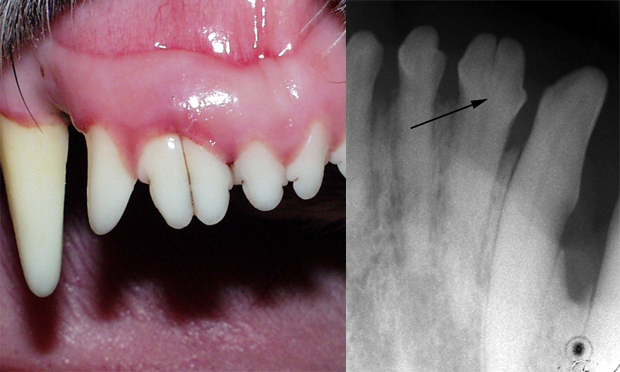

Case Study Fractured Upper Canine Tooth In Five Year Old Male Border Terrier Cross Vet Times

Exploring Tooth Fracture Risks In Canine Patients Vet Times